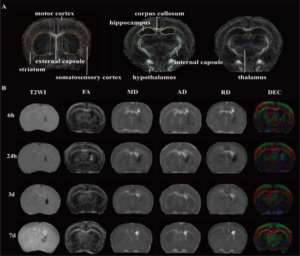

Preliminary feasibility study on DTI to assess the early brain injury in germinal matrix-intraventricular haemorrhage rats

Preliminary feasibility study on DTI to assess the early brain injury in germinal matrix-intraventricular hemorrhage rats